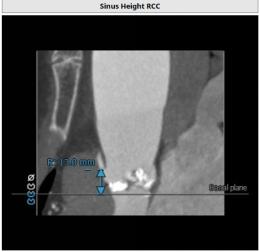

CT:

主动脉瓣Type 0型二叶瓣,瓣叶瓣缘结节样增厚伴中度钙化,开放受限。冠脉高度可。法式窦结构可,心脏角度约52°,左室较小,升主动脉未见明显扩张,右股动脉直径大于5.5mm,可作为主入路。患者为中度钙化的,重度主动脉瓣狭窄,呈鱼嘴型,结合主动脉根部结构,考虑植入Sapien 3瓣膜。

左冠高度

右冠高度